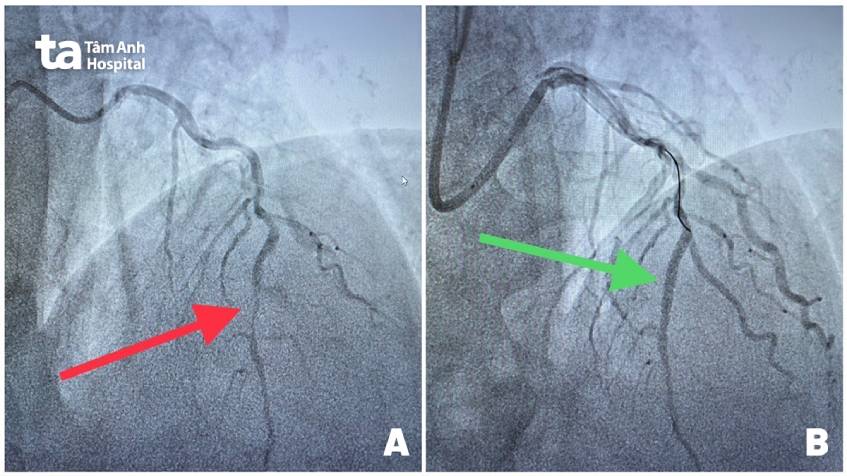

Khi bệnh nhân đến khoa cấp cứu, công tác nhận bệnh được thực hiện khẩn trương, chỉ trong vòng 5 phút, bệnh nhân được đưa lên phòng DSA để chụp mạch vành. Kết quả cho thấy 2 trong số 3 nhánh mạch máu chính nuôi tim đã tắc hoàn toàn, gây ra cơn nhồi máu cơ tim nặng. Nếu không kịp thời tái thông mạch máu, bệnh nhân có nguy cơ rối loạn huyết động, tụt huyết áp, giảm nhịp tim, sốc tim, ngưng tim do dòng máu nuôi tim bị chặn gần hết.

Ngay lập tức, bác sĩ Tuyến cùng ekip tiến hành nong mạch đặt stent tái thông hai nhánh mạch máu chính. Thử thách lớn nhất là bệnh nhân thừa cân – béo phì (cân nặng hơn 100 kg) khiến quá trình can thiệp qua da khó khăn hơn. Mọi thao tác cần hết sức khéo léo và chuẩn xác để không mất quá nhiều thời gian cứu những vùng cơ tim đang bị hoại tử. Sau 30 phút, dòng máu được khơi thông, tim có bóp bình thường, nhịp tim và huyết áp ổn định, triệu chứng đau ngực, khó thở của bệnh nhân được cải thiện.